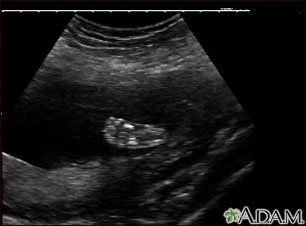

Ultrasound, normal fetus - foot

This is a normal ultrasound of a fetus at 19 weeks gestation. The right foot, including the developing bones, are clearly visible in the middle of the screen.